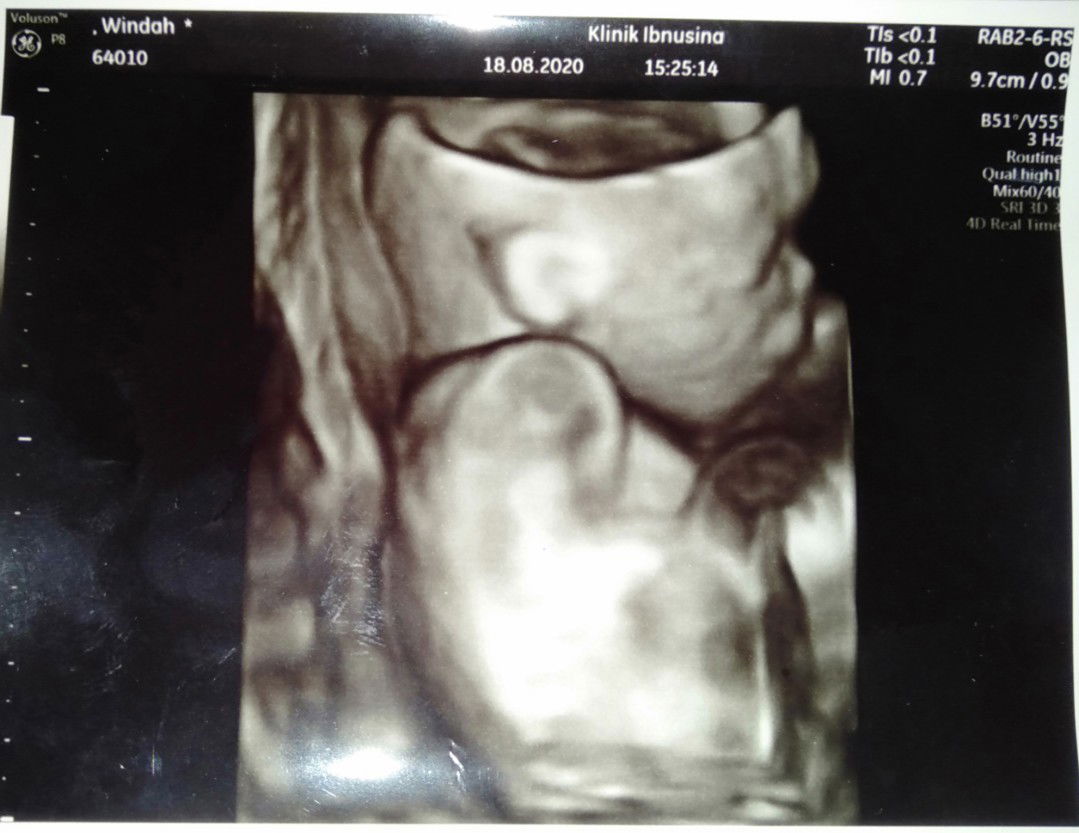

Bayi udah launching 😍

Alhamdulillah lahir anak pertama kami pada tanggal 26 agustus 2020 HPL 18 agustus 2020. Dengan BB 3.9 kg. Panjang 53 cm laki-laki#firstbaby .😍🤗